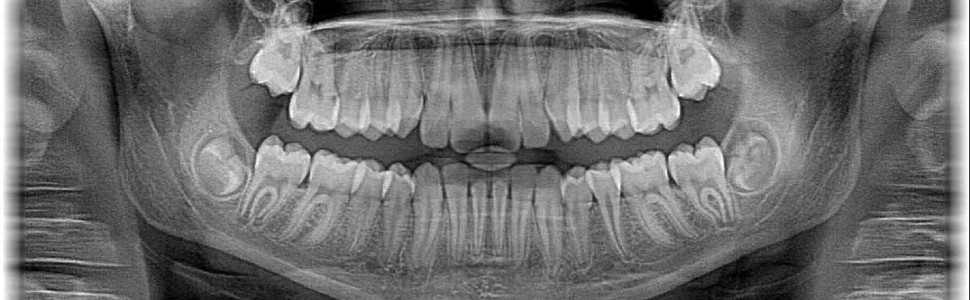

Aim of study. The purpose of the study was to test the ability to recognize human teeth and differentiate radiological images of dental materials on X-rays by English division students starting their second year of dental studies.

Method. Presentation of fourteen radiological images twice, with five-week interval and filling an anonymous questionnaire, assigning two answers to each X-ray.

Results. The better part of students identify the shark tooth and human permanent teeth. The X-rays of dog’s milk tooth and human milk teeth was a problem, the most difficult was the proper diagnosis of artificial teeth.

Conclusions. At the beginning of the radiology course students it was most difficult to identify radiological image of dental materials. An improvement in the ability to differentiate human teeth with other images was noted within 5 weeks of course.